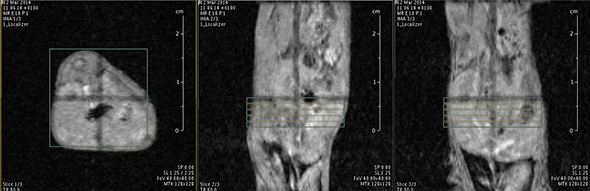

MRI is based on NMR Spectroscopy, which is the best language to talk to nature. We know how it is important to exploit different field strengths in order to extract maximum information from the system that we are investigating.

I think that also the low-field, let’s say the low/intermediate field to work at the 1 Tesla for instance as in the case of this beautiful Icon system, this gave us unique possibilities. Anytime we use a gadolinium-based agent or more in general a paramagnetic basic agent the best field is the 1 Tesla.

So, we can show that there is a real advantage of working at 1 Tesla in comparison to for instance 7 or 9 Tesla when one is using a relaxation enhancer to target a specific epitope in the region of interest.

Using the ICON™ Powerful MRI, Simplified.

For more information please visit: Bruker ICON™